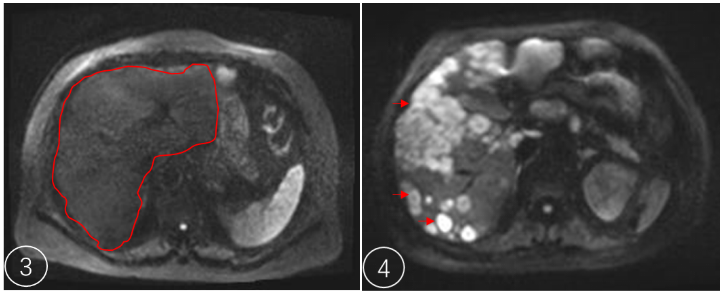

肝脏:区分血管瘤和恶性肿瘤

图3为肝脏正常DWI序列扫描表现(红色线圈勾画区域)

图4位肝脏肿瘤DWI序列扫描表现(箭头所指亮白色区域)